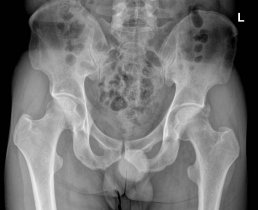

¹æ»ç¼± °Ë»ç :  ÁÂÃø °í°üÀý  ¿ÜÃø ¿Í¼ø°ú °üÀý³¶ºÎÀ§  ¼®È¸È­(+)(»çÁø10) * »çÁøÀ» Ŭ¸¯Çϸé ÇØ´ç »çÁøÀÌ º¸ÀÔ´Ï´Ù.